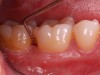

Clinical PPD is measured to the nearest millimeter by means of a graduated periodontal probe with a standardized tip diameter of approximately 0.4 mm to 0.5 mm. Several factors can influence the measurements made with periodontal probes, including: the thickness of the probe used5; the angulation and positioning of the probe depending on anatomic features, such as the contour of the tooth surface (Figure 1 through Figure 3)6; the graduation scale of the probe5; the pressure applied on the instrument during probing6; and the degree of inflammatory cell infiltration in the soft tissue and accompanying loss of collagen.7

Fig 1. Inaccurate probing angle wrongly indicates probing depth at 3 mm, which does not correspond to the radiographic finding shown in Fig 2.

Fig 3. Correct angulation of the probe demonstrates 6-mm probing depth.